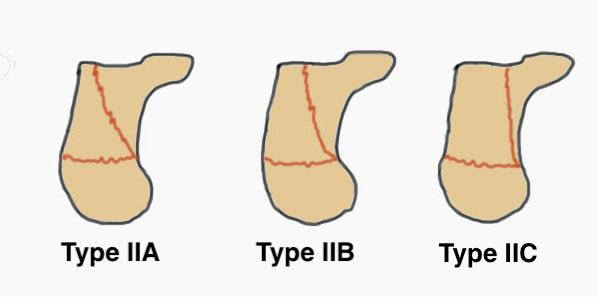

Sanders Coronal CT Classification

Posterior facet on coronal CT

- number of longitudinal fracture lines (Type II - IV)

- location of fractures (A: lateral, B: central, C: medial)

| Type I | Type II | Type III | Type IV |

|---|---|---|---|

| Undisplaced |

Two parts Displaced > 2 mm |

Three parts Displaced > 2 mm |

Highly comminuted |

| Non operative | ORIF | ORIF / fusion | Primary fusion |

|

|

|